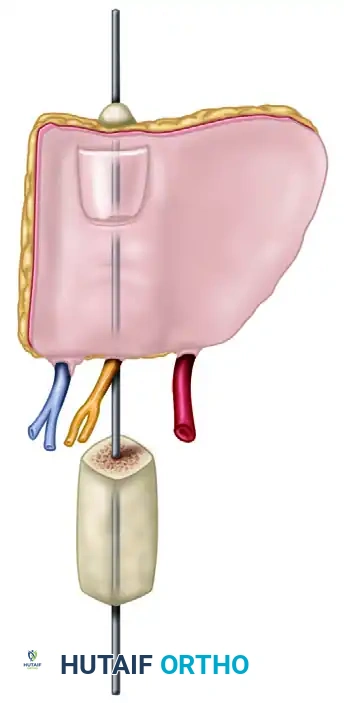

Bone and Nail Harvest

- Separate the toe flap beneath the nail by gentle, sharp subperiosteal elevation.

Pitfall: Avoid any injury to the germinative layer of the nail matrix. Damage here will result in a deformed or absent nail on the reconstructed thumb.

- Using a fine osteotome or bone cutter, remove approximately 1 cm of the distal tuft of the distal phalanx, keeping it attached to the flap beneath the nail bed. This bone segment provides rigid support for the nail complex.

Flap Isolation

At this stage, the flap should be completely free from the toe, tethered only by its neurovascular pedicle (the dorsal digital branches of the FDMA and the saphenous venous tributaries).

Release the tourniquet. Confirm that the flap is adequately perfused by its arteriovenous pedicle.

* Note: It may take 30 to 60 minutes for the flap to turn completely pink due to vasospasm. Bathing the vessels in warm saline and topical lidocaine or papaverine is highly recommended to relieve spasm.

Once perfusion is confirmed and the recipient hand is fully prepared, apply microvascular clips to the vessels. Ligate or apply small hemoclips to the proximal vessels before sectioning them to harvest the flap.